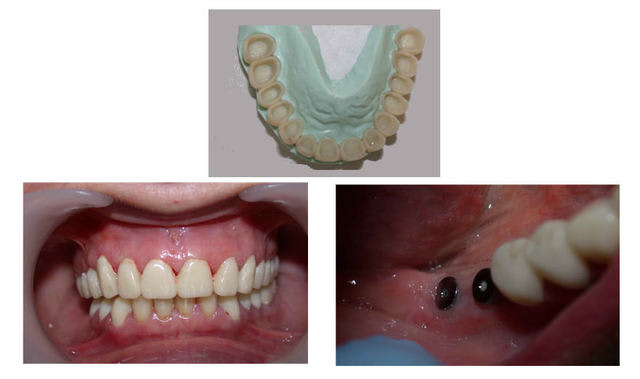

l'atteinte coronaire était telle que l'on voyait la pulpe par transparence ....

J'suis pas convaincu d'autant que tu as augmenté la DVO.

pour te convaincre si j'y arrive .

Je ne sais si j'ai sauté un épisode,mais il aurait été interessant de voir le bridge définitif en occlusion,je n'ai vu que le provisoire

demain je posterai une photo du bridge en occlusion pour faire plaisir à annie .

pour annie ...

au passage en comparant photo initiale et celle ci après réalisation prothétique le recentrage des milieux est presque bien...